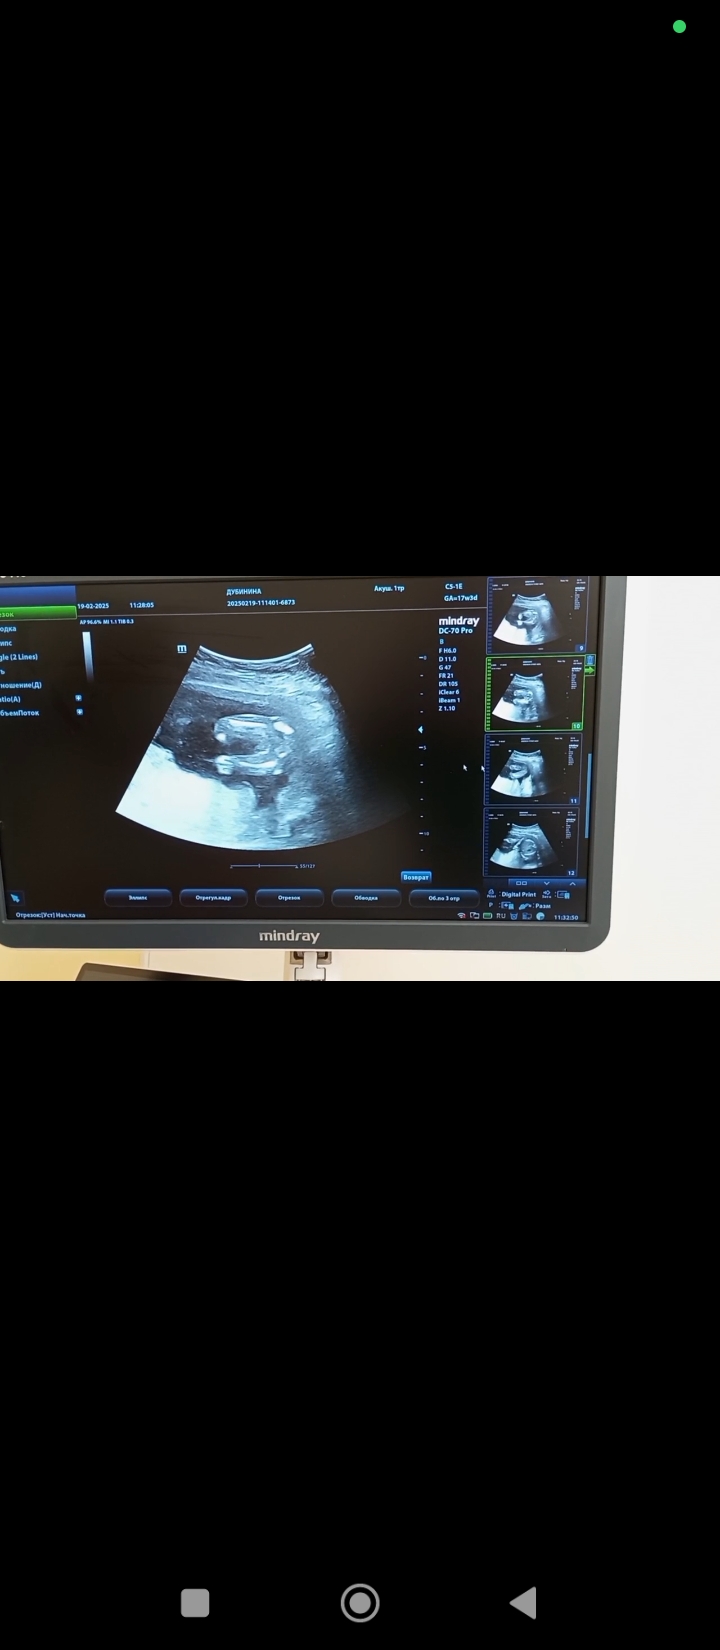

Валентина в Благополучная беременность 9 месяцев Пол Пол малыша Пол на 17 недели. Кто там? Посмотрите еще 20 записей на эту тему Отменить Ответить Ирина Лапина Мальчик🙂 27.02.2025 Ответить Чашка утреннего кофе Мальчик - мошонку видно, у девочек такого нет)) 27.02.2025 Ответить Валентина Чашка утреннего кофе, 27.02.2025 Ответить Виктория Я думаю девочка, у мальчиков сильнее торчит) 27.02.2025 Ответить Валентина Виктория, 27.02.2025 Ответить Виктория Валентина, девочка) 27.02.2025 Ответить Tatiana И я за мальчика. 27.02.2025 Ответить Ornella Mutit Предположу мальчика🩵 27.02.2025 Ответить Mari Я думаю мальчишка) у моей на таком же фото ничего не было между ножек) . 27.02.2025 Ответить Валентина Mari, здесь тоже ничего нет 27.02.2025 Ответить Mari Валентина, значит на том фото показалось) мелкое очень. Теперь вижу, что ничего нет) ну значит, девочка☺ 27.02.2025 Ответить Виктория Я за девочку 27.02.2025 Ответить Юля А мне кажется что мальчик ... 27.02.2025 Ответить Татьяна Мне кажется девочка 😁 У моего на такой фотке прям торчал корнишон😆 27.02.2025 Ответить Мальчик же? Пол мальчик или девочка? Чаты Беременных Выберите чат: Январята-2026 Февралята-2026 Мартята-2026 Апрелята-2026 Майчата-2026 Июнята-2026 Июлята-2026 Августята-2026